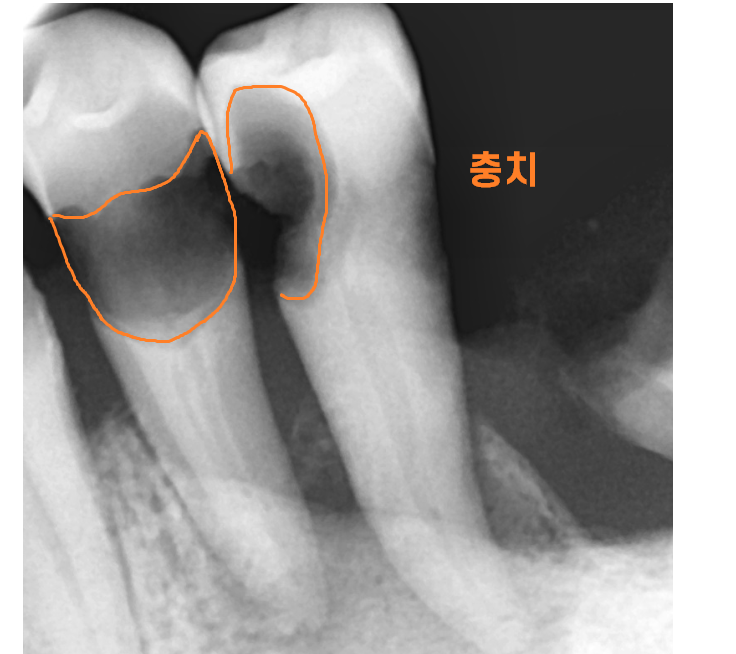

x ray를 추가적으로 찍게 되고

ct등을 통하여 임플란트 수술 계획이 결정되는데요.

임플란트는 뼈에 식립하기 때문에

골밀도와 잇몸 상태를 고려해 수술 방식을 결정해야합니다.

이에 따라 임플란트 재료도 달라질 수 있고

필요 시에 따라 잇몸치료나 뼈 이식이 진행될 수도 있습니다.

사실상 진단만으로도 임플란트 식립 사이즈 , 개수 등이

결정된답니다.

오늘 환자분도 골밀도를 분석하여

남아있는 뼈의 양을 측정

임플란트 사이즈까지 적어 왜 뼈이식이 필요한지

설명드렸었거든요~~